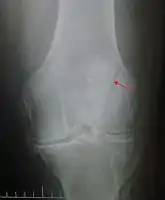

The patella can break in various ways depending on the way it is injured, and into two or more pieces.[1] Types include transverse, the most common, with one fracture line;[5] marginal; osteochondral; and the rare vertical type, or stellate, where a direct compression force gives rise to a comminuted pattern.[5][7] Patella fractures can be further classified as displaced, where the broken ends of bone do not line up correctly and separate by more than 2mm, or undisplaced and stable where pieces of bone remain in contact with each other.[1][7] If fragments of patella bone stick out from the skin it is known as an open patella fracture, and closed if the overlying skin is intact.[1]

Transverse fracture of patella